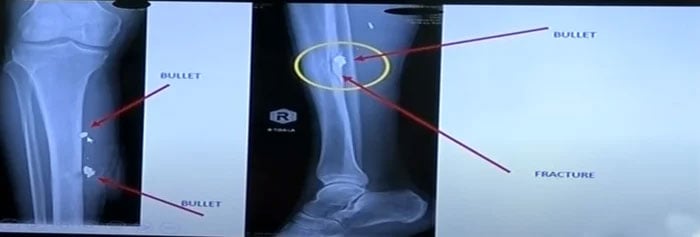

Dr Sultan displayed Khan's X-ray reports on a screen and highlighted the details of the injuries that the party chief sustained — including a fracture — among other injuries.

Image showing an X-ray of Khans shin. — Screengrab via YouTube/ Geo News Live

Image showing an X-ray of Khan's shin. — Screengrab via YouTube/ Geo News Live